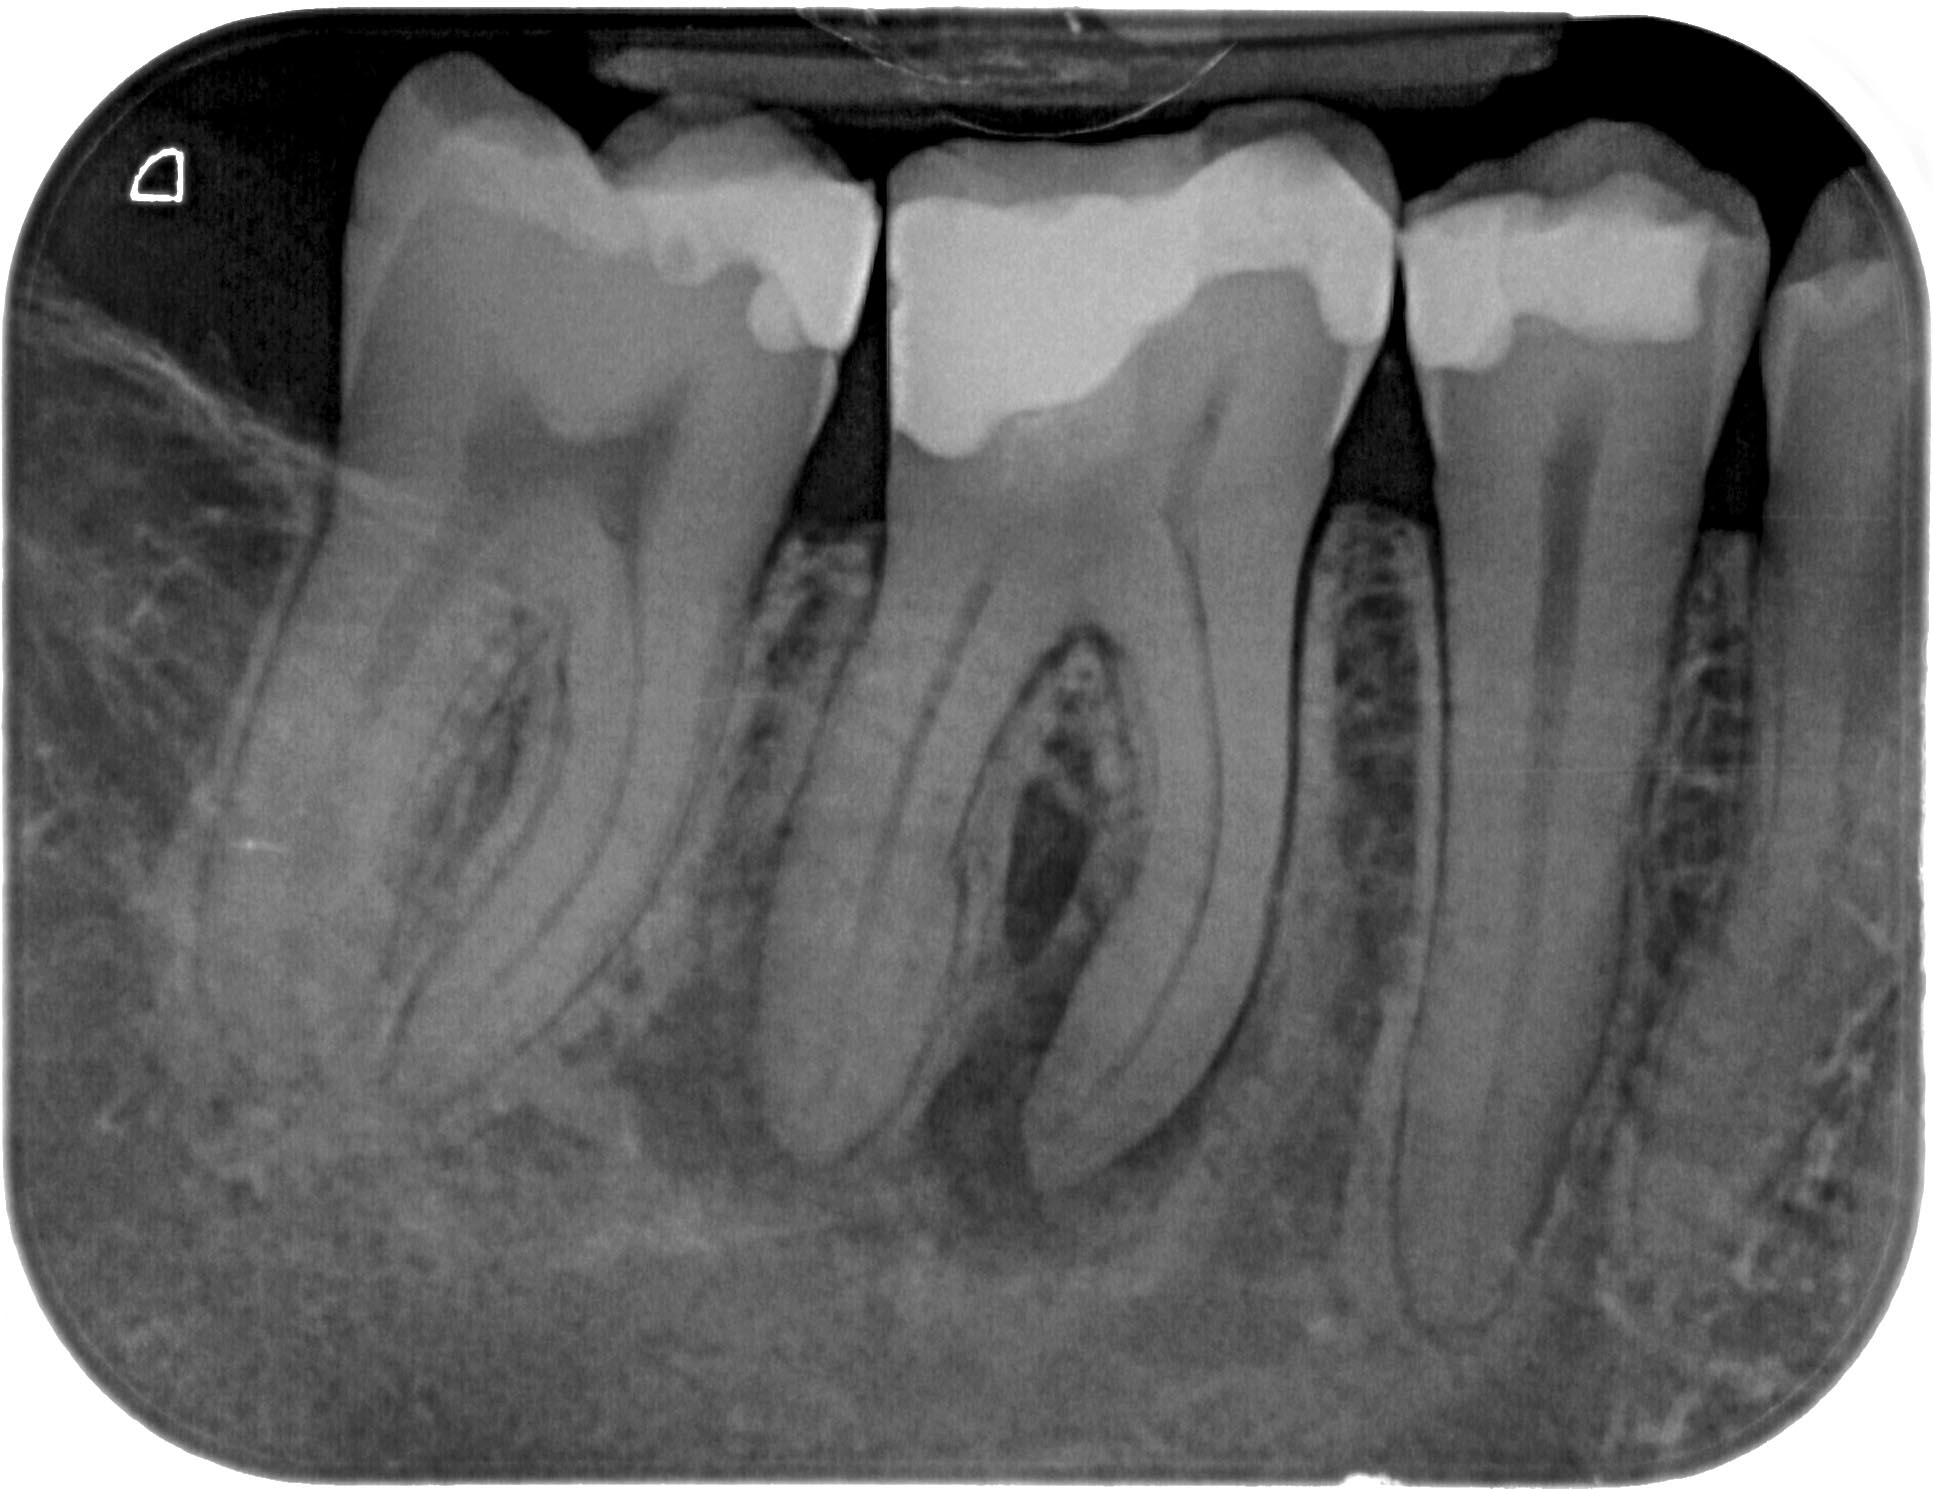

WS46 (1 von 4) Veröffentlicht 21. März 2016 am 1933 × 1489 in Calciumhydroxid- Überpressung (2) 12. Juni 2012